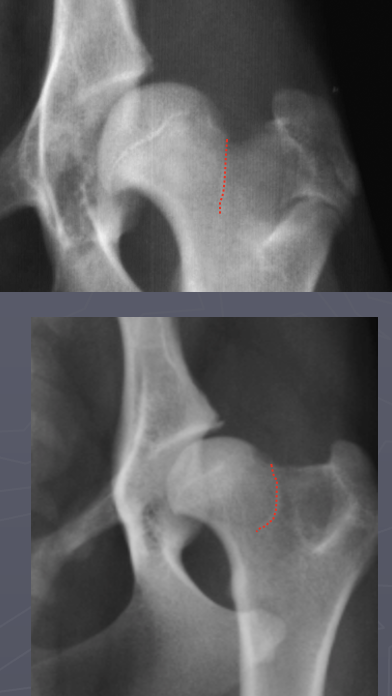

What is shown in these radiographs?

A

hip dysplasia

-minimal coverage of femoral head

-flattened, sclerotic femoral head

-no femoral neck present

-osteophyte formation and sclerosis

What is outlined in these radiographs?

Morgan’s line